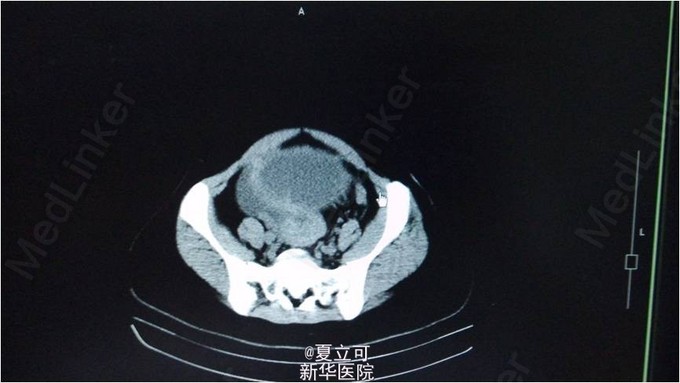

患者,女,21岁。患者1月无明显诱因下出现阵发性左下腹痛,疼痛为刺痛,伴有纳差、恶心感,无呕吐,无发热、腹泻、反酸等。 查体:腹平软,脐周偏左压痛,无反跳痛及肌卫,肝脾肋下未及,移动性浊音阴性,肠鸣音正常。 辅助检查:血常规:CRP 38mg/L,白细胞计数 10.21 10^9/L,肝肾功能、电解质、心肌酶谱、肿瘤指标均未见明显异常。 诊断:左卵巢浆液性囊腺瘤伴出血坏死 治疗过程及结果:入院后1天,患突发全腹疼痛,伴有大汗、心悸不适,当时心率103次/分,血压138/85mmHg。查体:腹紧张,压痛,腹部可及巨大包块,质软。急查腹部CT平扫:腹盆腔巨大囊性占位。阴超:巨大盆腹腔囊性包块,宫底部前方实性包块,腹水。腹部MRI:左下腹及盆腔可见巨大囊性病灶,大小约19*13*23cm。考虑左侧卵巢来源囊腺瘤。后于全麻下行腹腔镜探查+腹腔镜左附件切除+粘连松解术,术中冰冻:左卵巢浆液性囊腺瘤伴出血坏死。术后抗炎补液等对症支持治疗后,症状好转出院。 随访一个月未在出现腹痛症状。 经验:该患者为年轻女性,以反复左下腹痛入院,除消化道疾病外还需考虑妇科疾病,如宫外孕、卵巢囊肿等。该患者虽外院检查提示妇科超声未见明显异常,但最终证实为卵巢囊肿蒂扭转,故提示在临床工作中,不能过分依赖辅助检查,仍应以对病人临床症状观察为主导,结合相关辅助检查协助诊治,必要时复查相关检查十分重要。该病例诊治过程中处置及时,故预后好。